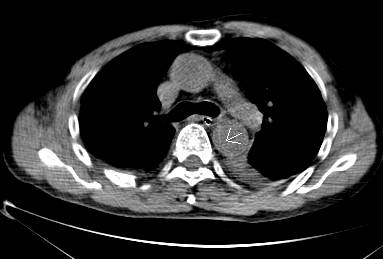

平扫CT提示降主动脉内膜片影(白箭头所示),CTA显示为B型主动脉夹层。